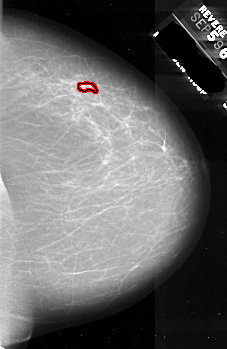

A_1075_1.RIGHT_MLO

RIGHT_MLO LINES 6706 PIXELS_PER_LINE 4231 BITS_PER_PIXEL 16 RESOLUTION 42 OVERLAY

FILE: A_1075_1.RIGHT_MLO.OVERLAY

TOTAL_ABNORMALITIES 1

ABNORMALITY 1

LESION_TYPE CALCIFICATION TYPE PLEOMORPHIC DISTRIBUTION CLUSTERED

ASSESSMENT 4

SUBTLETY 2

PATHOLOGY MALIGNANT

TOTAL_OUTLINES 1

BOUNDARY